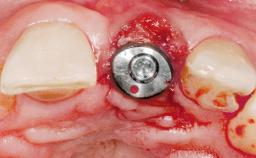

Immediate Placement of an Implant in a Maxillary Left Central Incisor Site

Type of Implants One-Piece

Bone Augmentation Horizontal|Simultaneous

Augmentation Materials Xenogenous|Membrane

Placement Protocol Immediate implant placement

Socket Integrity Damage to one or more bone walls

Bone Volume Damage to one or more socket walls